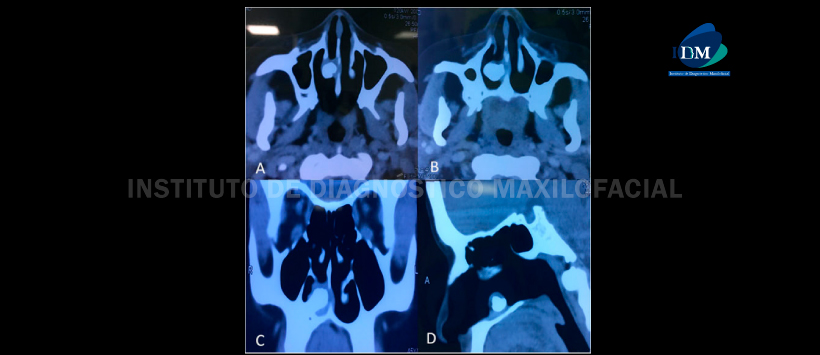

La tomografía computarizada mostró una masa lisa ubicada en el piso de la cavidad nasal derecha entre el cornete inferior y

tabique nasal, con una alta atenuación homogénea equivalente al de los dientes (Fig. 1).

La misa fue rodeado de tejidos blandos, consistente con la clínica y hallazgo de tejido de granulación.